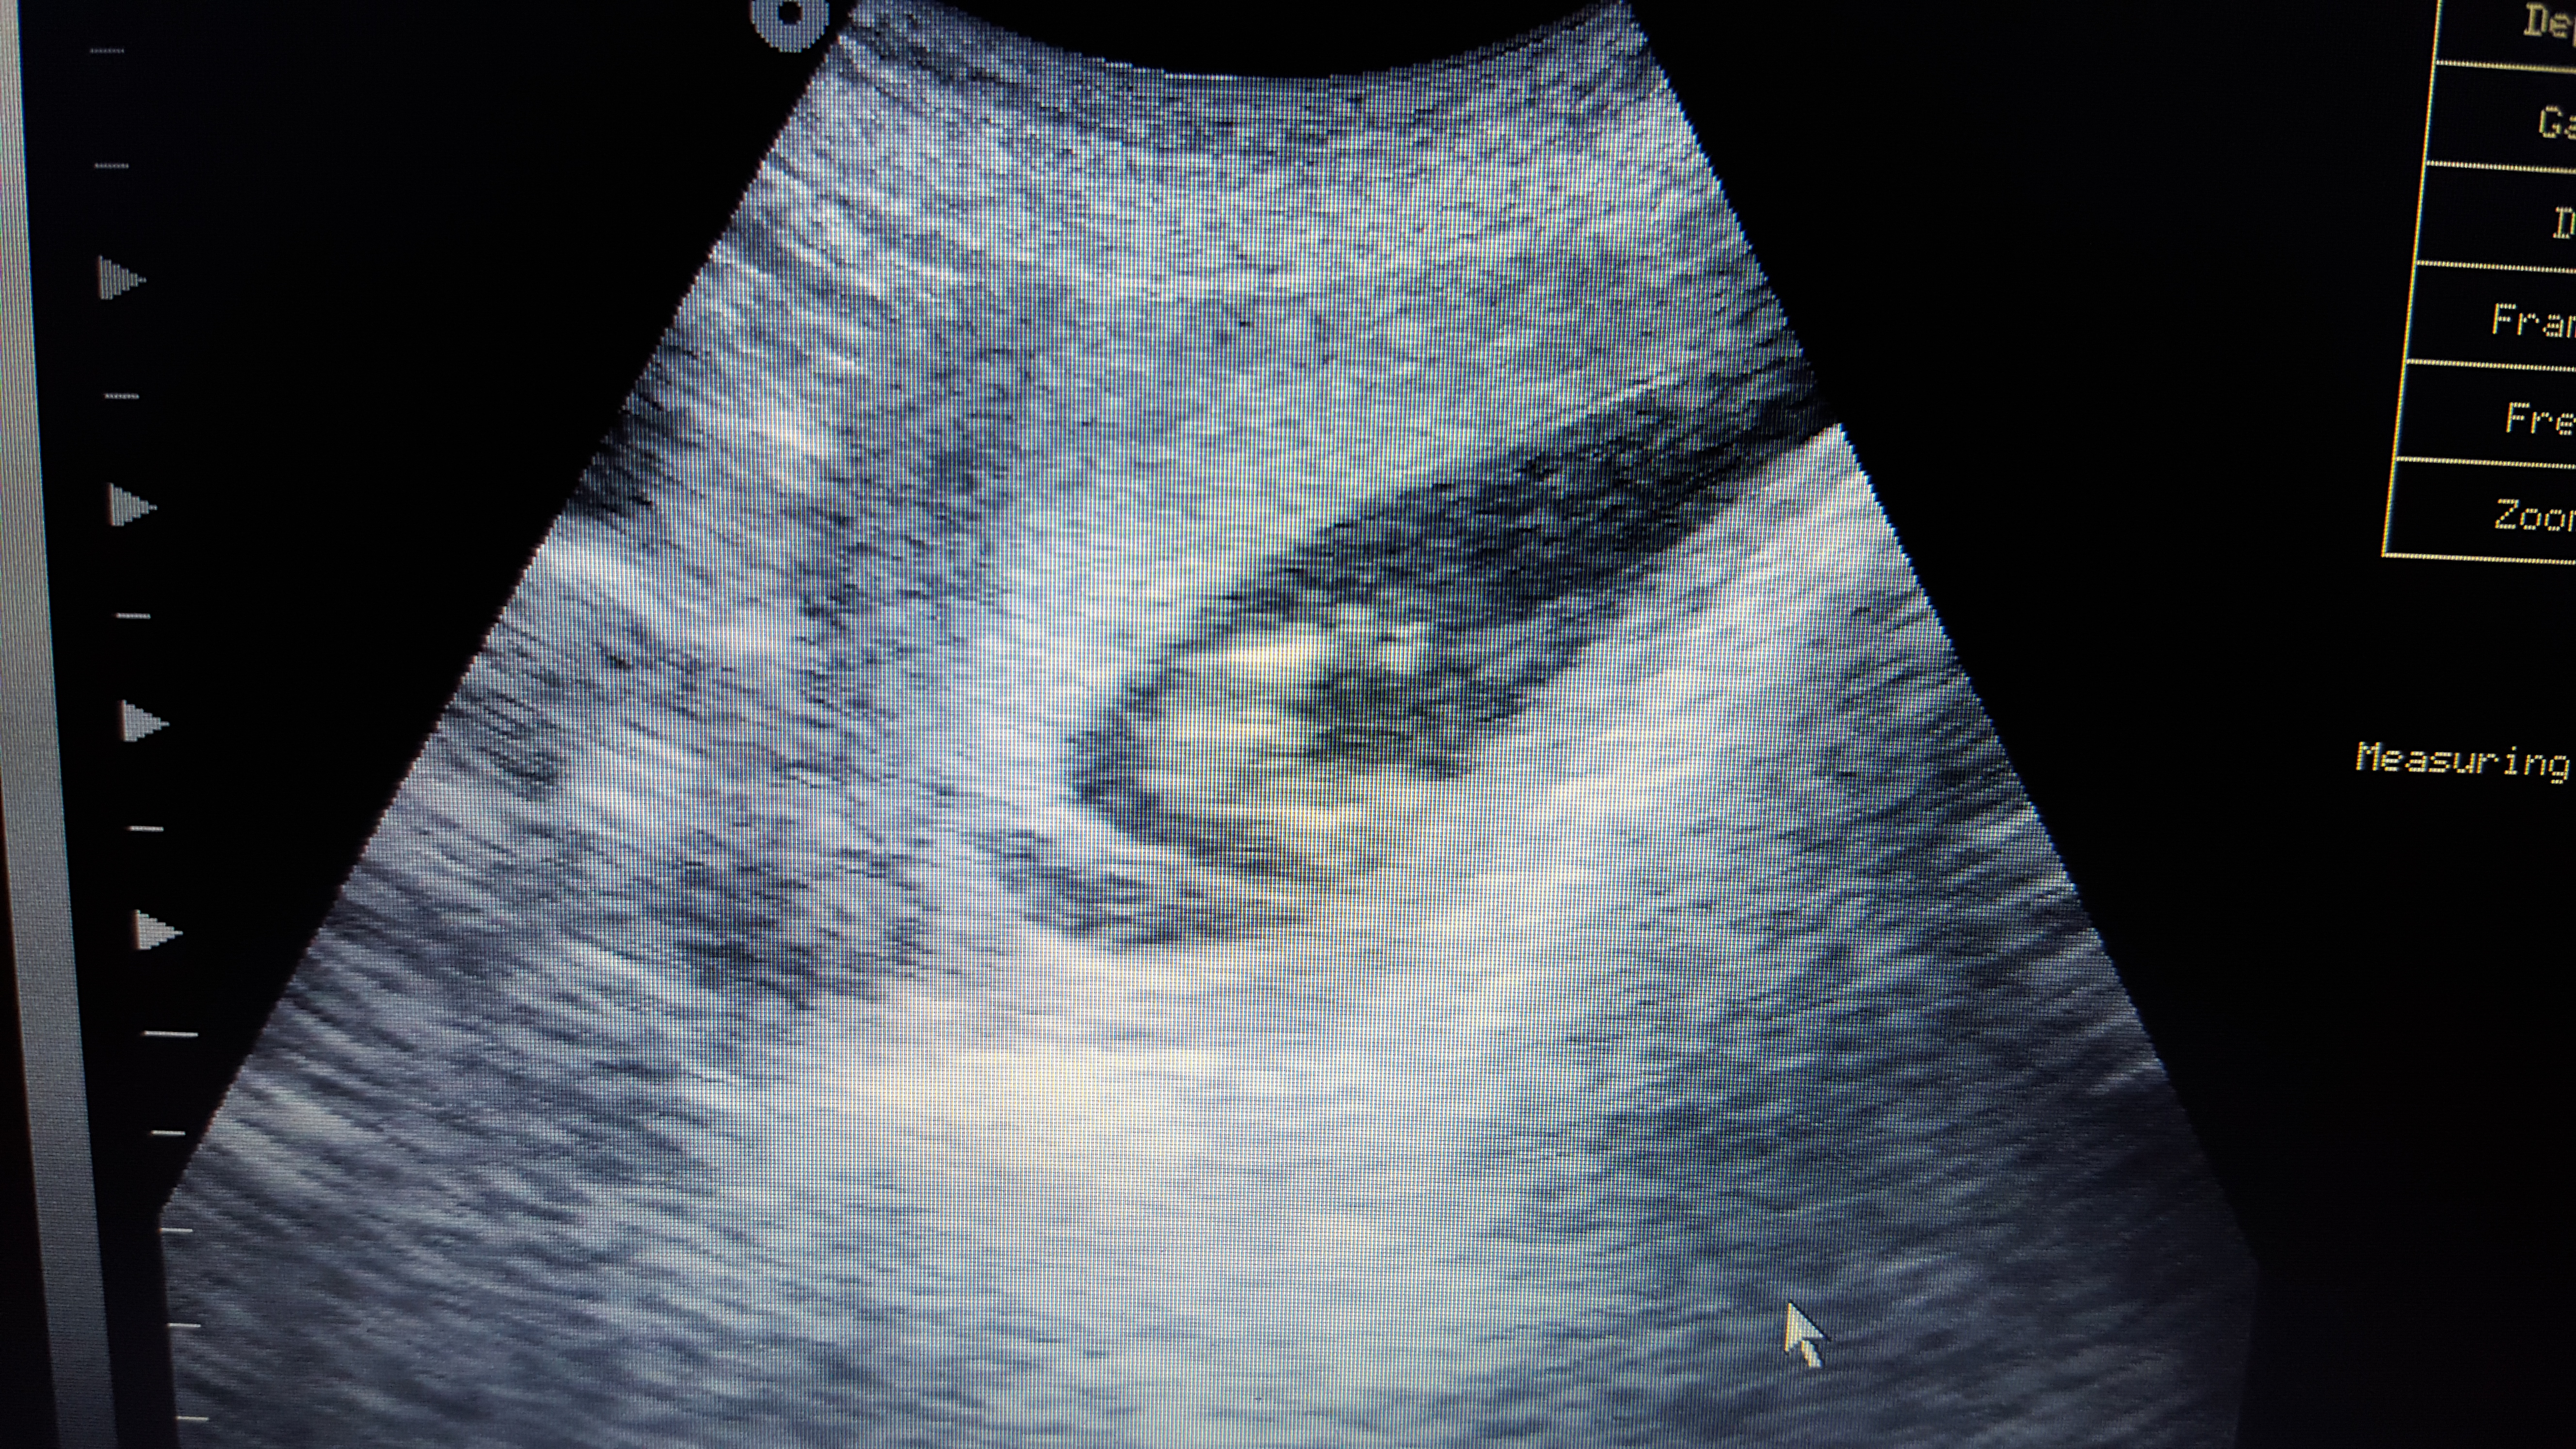

Pink or blue? These are taken at 13+3

Attachment 29186

Babies hands were around genital area alot so may of caught that in some of the photos!